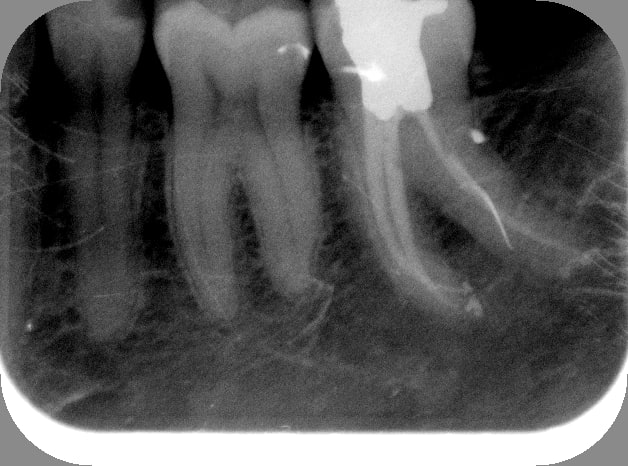

Par honnêteté, sur la 37, j'ai dû négocier l'apex du MV en manuel.

Pour exemple, sur la 37, je commençais à être mal à l'aise et ai hésité à changer de lime avant la fin. Mais longueur de travail importante+courbure, j'ai dû récapituler 3 fois S1+R25 avant d'arriver à l'apex.

(et edit parce que je n'y avais pas fait attention, le machin radio opaque en distal, c'est un artefact hein, mes films digora sont dégueulasses mais j'ai rien cassé aujourd'hui)